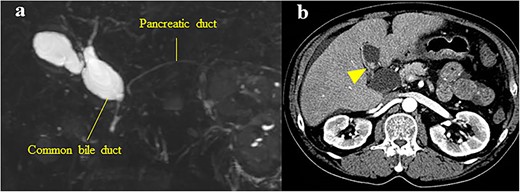

The patient was a 62-year-old man who was diagnosed with PBM with Type Ia CBD 4 years previously (Fig. 3a). On magnetic resonance cholangiopancreatography (MRCP), the largest diameter of the common bile duct was 29 mm. However, the patient refused treatment and underwent follow-up observation alone. He visited the hospital regularly and underwent serum tumor marker tests and imaging (CECT or MRCP) annually despite the absence of symptoms. Approximately, 4 years after his diagnosis, gallbladder cancer was detected on CECT, which was performed as part of the regular follow-up examination for PBM. The patient had a previous medical history of alcoholic cirrhosis (Child–Pugh B), diabetes mellitus and hypertension. Laboratory examinations revealed the following values: platelet count, 9.5 × 104/μl; aspartate transaminase, 47 U/l; gamma-glutamyltransferase, 138 U/l; total bilirubin, 1.4 mg/dl; albumin, 3.4 g/dl; prothrombin time, 65%; carcinoembryonic antigen, 10.4 ng/ml; carbohydrate antigen 19–9, <2 U/ml and duke pancreatic monoclonal antigen type 2, 570 U/ml. In the current examination, contrast-enhanced CT revealed an 11-mm mass with a contrast effect in the gallbladder despite the absence of a mass 4 years previously (Fig. 3b). The patient then underwent extrahepatic bile duct resection and cholecystectomy. The gallbladder had atrophied and had been buried in the liver (Fig. 4a and b). The amylase level in the bile samples collected from the gallbladder and common bile duct were 6590 and 15 270 U/l, respectively. A pathological examination revealed well-differentiated adenocarcinoma of the gall bladder without bile duct involvement (T1aN0M0 Stage I) (Fig. 4c). R0 resection was performed. However, the patient developed hepatic failure, refractory ascites and spontaneous bacterial peritonitis after surgery and died of sepsis after 4 months.

(a) MRCP showing PBM with Type Ia CBD; the largest diameter of the common bile duct was 29 mm; (b) CECT showing an 11-mm mass with a contrast effect in the gallbladder (arrowhead).